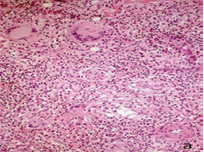

Figure 4a This nerve is surrounded by granulomas and lymphocytes but its structure looks normal.

Figure 4b It is not easy to determine if this nerve is being infiltrated and destroyed by the cellular reaction or if it is simply surrounded by it.

Figure 4c Well preserved nerve with a giant cell, scant macrophages and some lymphocytes in the endoneurium. A-C: HE. A,10 X. B, 16 X. C, 40 X.

Some giant cells and macrophages touched the nerve or penetrate the endoneurium and distorted neural architecture (Figures 3,4). Other cutaneous nerves were located at the center of the infiltrate and looked well preserved (Figure 5).